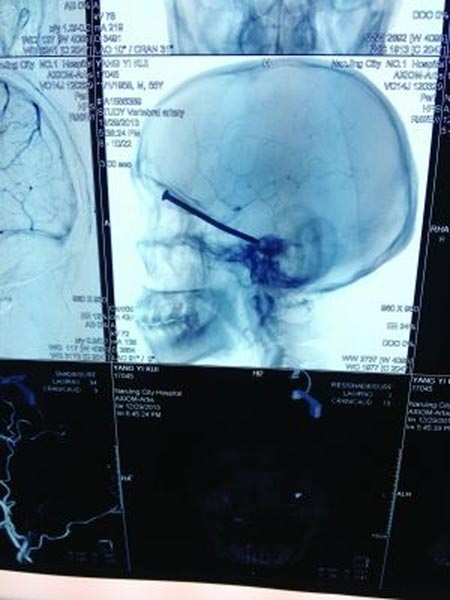

Tuy nhiên, sự việc trở nên nghiêm trọng hơn khi sáng hôm sau tỉnh dậy, Yang thấy đầu đau ê ẩm và mắt sưng. Sau khi tới bệnh viện, các bác sĩ nói rằng, một chiếc đinh dài 8 cm đã cắm vào hộp sọ của Yang.

| Chiếc đinh dài tới 8 cm cắm vào hộp sọ ông Yang. Ảnh: Want China Times. |

“Thật may mắn, chiếc đinh không chặn các mạch máu quan trọng dẫn tới não. Đây là điều hiếm gặp. Bệnh nhân vô cùng may mắn”, bác sĩ điều trị cho Yang nói.